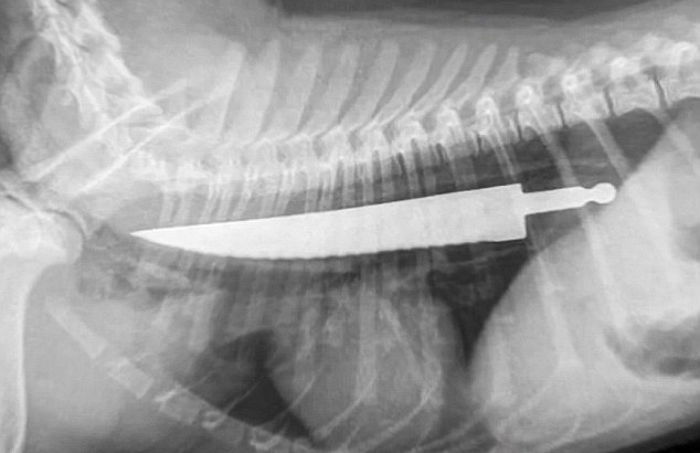

[인사이트] 김선혜 기자 = 6개월 된 어린 강아지가 자신의 몸 절반 정도 크기인 20cm 짜리 '칼'을 집어삼켜 간신히 살아났다.지난 21일(현지 시간) 영국 일간 데일리 메일은 스테이크 칼을 삼키고도 무사히 살아난 행운의 강아지 렉시(Lexie)에 대해 소개했다. 사고...

20cm 짜리 ‘칼’ 삼키고도 살아난 강아지 (사진)